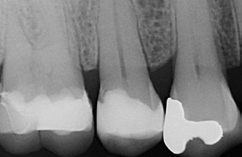

Die Weiterversorgung erfolgte nach adhäsiver Vorbehandlung mit einem approximal eingebrachten 4-mm-Inkrement SDR flow+ (Dentsply Sirona) in der Farbe A3, klassisch überschichtet mit ceram.x universal in der Farbe A3,5. Die Wahl auf ein Bulk-Flow-Komposit approximal fiel aufgrund der optimalen selbstnivellierenden Adhäsion zum Adhäsiv und somit zur Reduktion potenzieller Fehlerquellen in der Schichttechnik, die Wahl zugunsten des eingefärbten SDR flow+ in der Farbe A3 entgegen der transluzenten Universalfarbe U aufgrund der im Approximalraum dunkel erscheinenden Gold-Restauration am Nachbarzahn. Dies ergab in der Vergangenheit bei Verwendung von SDR flow+ U oft ein unschönes „grau-transluzent“ erscheinendes Bild der Kompositrestauration im Approximalraum. Ästhetisch störte dies meist nur bedingt, suggerierte aber immer die latente Möglichkeit einer Approximalkaries. Durch die Verwendung der Farbe A3 bei SDR flow+ war ein derartiges grau-transluzentes Erscheinungsbild nicht mehr gegeben; die Restauration erscheint homogener (Abb. 5). Die Abbildung 6 zeigt die Röntgenkontrollaufnahme nach einem Jahr, die Abbildung 7 die klinische Situation: Der Zahn ist weiterhin vital, symptomlos und beschwerdefrei. Direkte Kompositrestaurationen stellen heute gerade bei vorangegangenen Goldinlay-Kavitäten die suffizienteste Sekundärversorgung dar: Der vorhandene Federrand kann belassen werden und muss nicht in eine plane Stufe einer Keramikrestauration umpräpariert werden.

Im Röntgenbild ist kein Unterschied in der Röntgenopazität zwischen SDR flow+ und ceram.x universal auszumachen, obwohl 2/3 der approximalen Kavitätentiefe von SDR flow+ ausgefüllt wird. Da hinsichtlich ihres Indikationsspektrums direkte Kompositrestaurationen eine ideale Alternative zu Inlayversorgungen darstellen und zudem substanzschonender sowie kosteneffizienter sind, bleibt heute kaum mehr eine wahre Indikation für Inlayversorgungen. Klinisch bewährt hat sich die direkte Kompositversorgung gerade bei dem Austausch kleinerer Goldinlays [13,14].